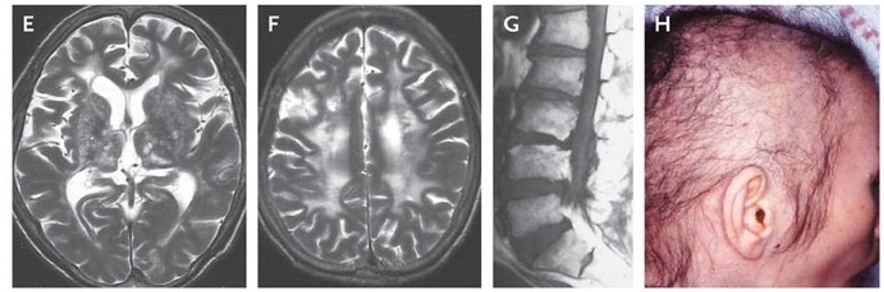

Gelastic seizures, marked by bouts of uncontrollable laughter, are classically linked to hypothalamic hamartomas. They may also be associated with Pallister-Hall syndrome (caused by a GLI3 mutation on chromosome 7). Present in infancy. EEG often normal due to deep seizure focus.